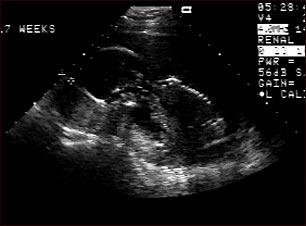

Ultrasonido de un feto normal; vista de perfil

Ultrasonido normal a las 17 semanas de gestación en que se observa el perfil del feto en el centro de la pantalla. El contorno de la cabeza con el rostro hacia abajo se aprecia en la parte central izquierda y el cuerpo en posición fetal se ve a partir de la parte inferior derecha de la cabeza. El perfil de la columna vertebral se dibuja en la parte central derecha de la pantalla.